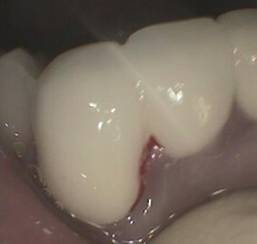

美容歯科(クイック矯正)ブリッジ

おそらく叢生(歯が重なって生えている)があったと考えられます。右下 2 番(側切歯)は抜歯されています。また支えとなっている歯 4 本のうち 3 本は神経を取っています。歯の角度を変えるためには大きく削りますがそのために神経を取る必要があったのかもしれません。抜歯された部分は歯を配列するスペース確保のためでしょうか。 写真の赤↓のある部分が抜歯された部分でダミーが入っています。このダミー部が清掃性不良でダミーの下は腫れた歯肉で塞いでいます。少しさわるだけで出血があります。